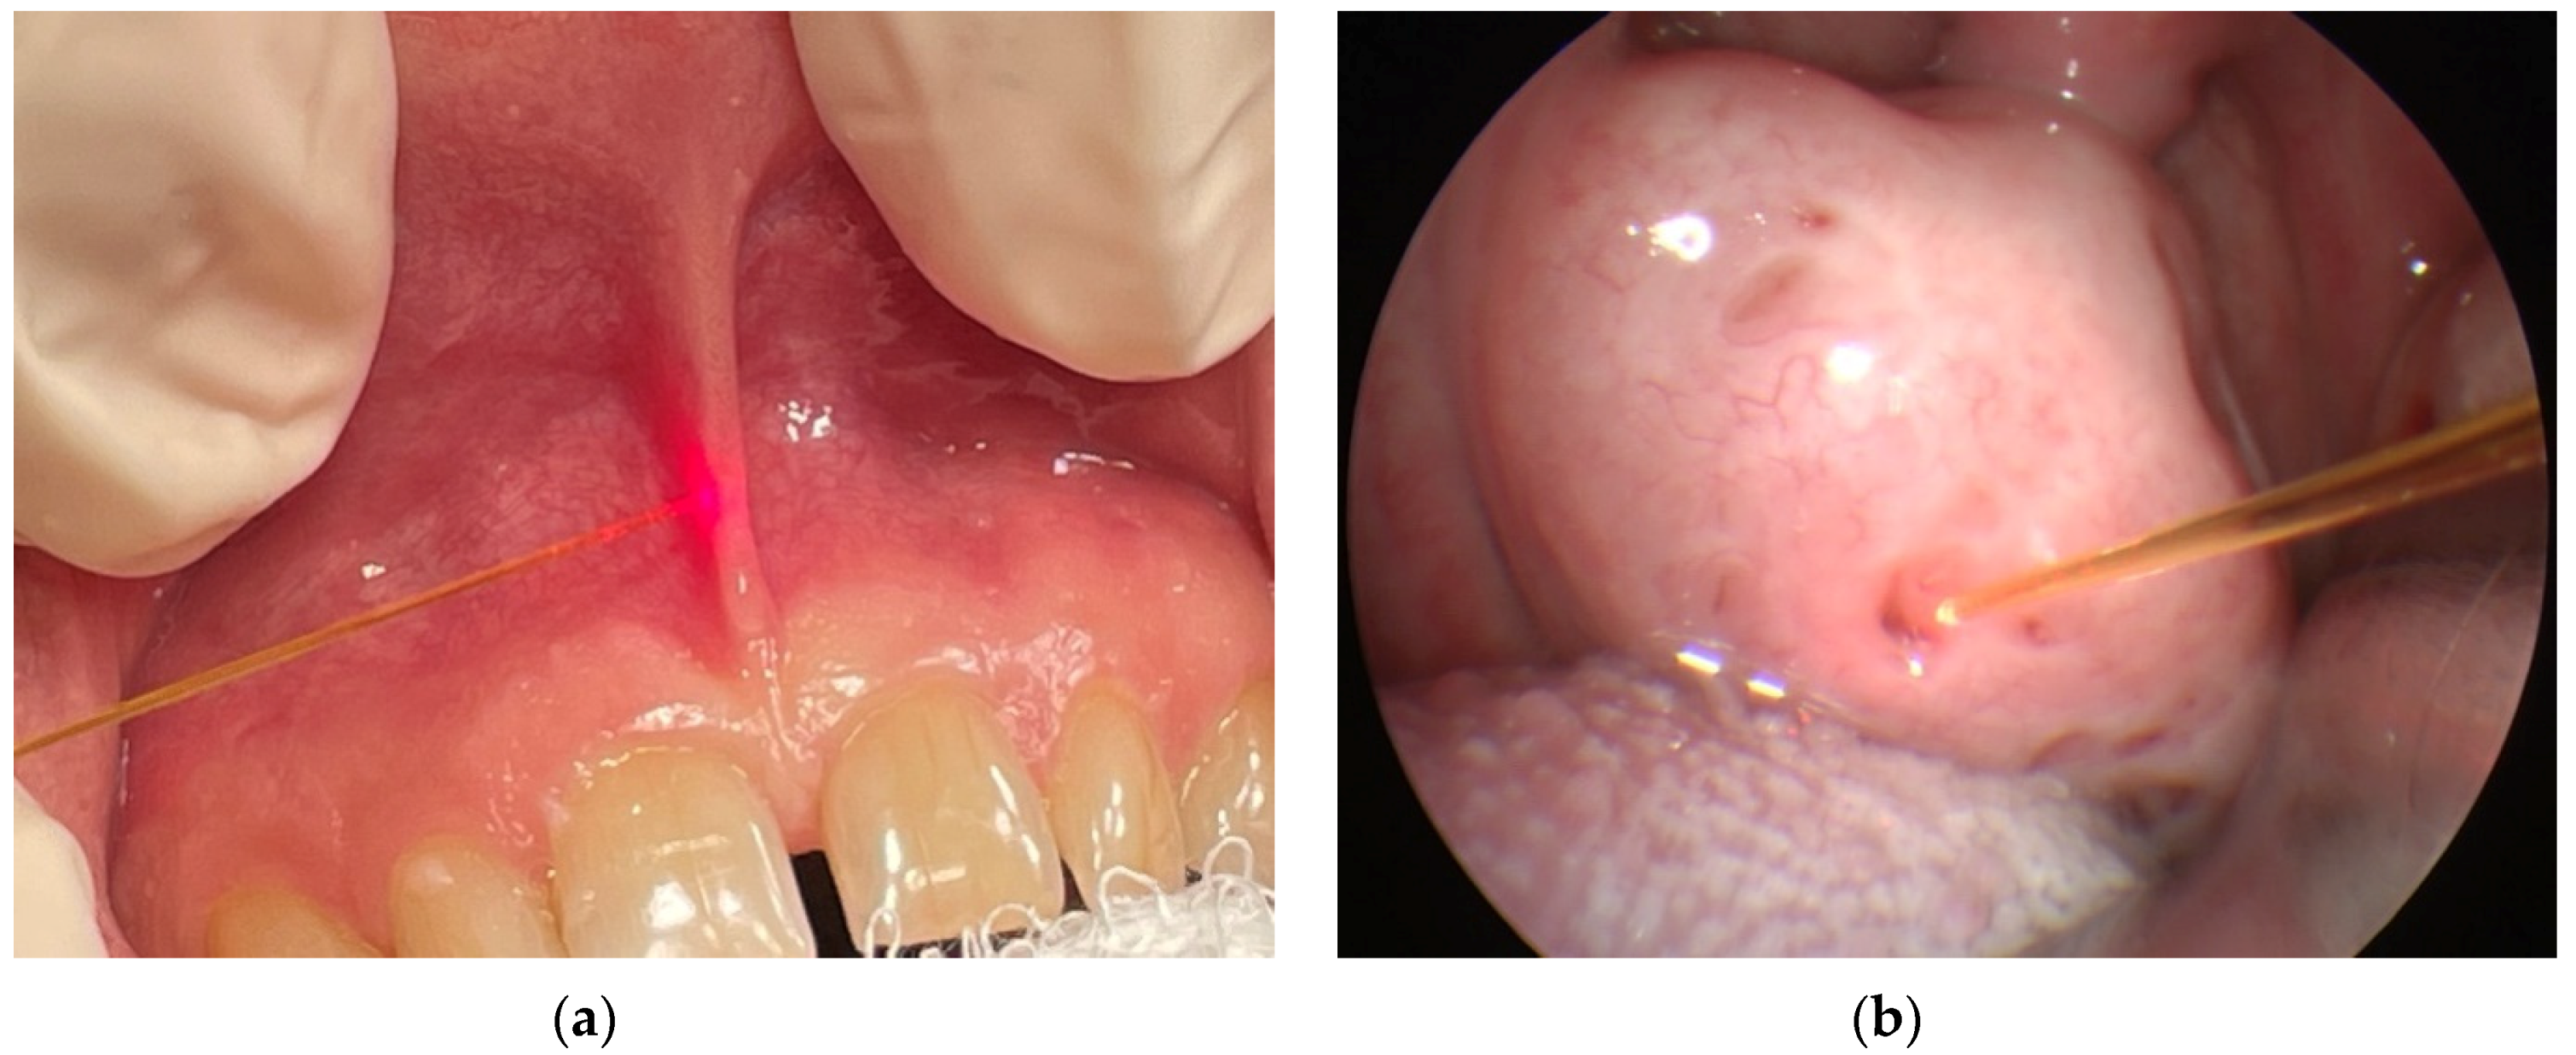

3.1. Pulsed Diode Laser 810 nm (5 W Fluence and Pulse Duration 4 s) in Laryngology Applications in MML Centre

| 5 W, τ = 4 s | Laryngology: laser-assisted somnoplasty, frenuloplasty, closure of tonsillar crypts, haemostasis, removal of cancerous changes, blepharoplasty, surgery of laryngopharynx and larynx, separation of adhesions in nasal septum | here | |